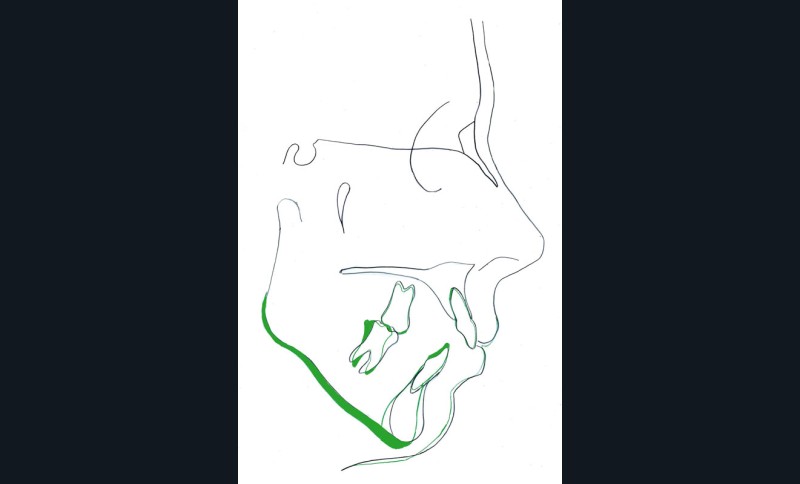

Diagnostic (fig. 1)

Cette patiente de 29 ans consulte pour des raisons principalement fonctionnelles mais également esthétiques. Elle présente :

– une classe II squelettique hyperdivergente

– une endognathie maxillaire

– une classe II division 1 majeure et asymétrique associée à une béance antérieure sévère

– un profil très convexe avec une occlusion labiale difficile et une biprochéilie

– une DDM par défaut modérée, maxillaire et mandibulaire

– des troubles de la posture et de la fonction linguale.